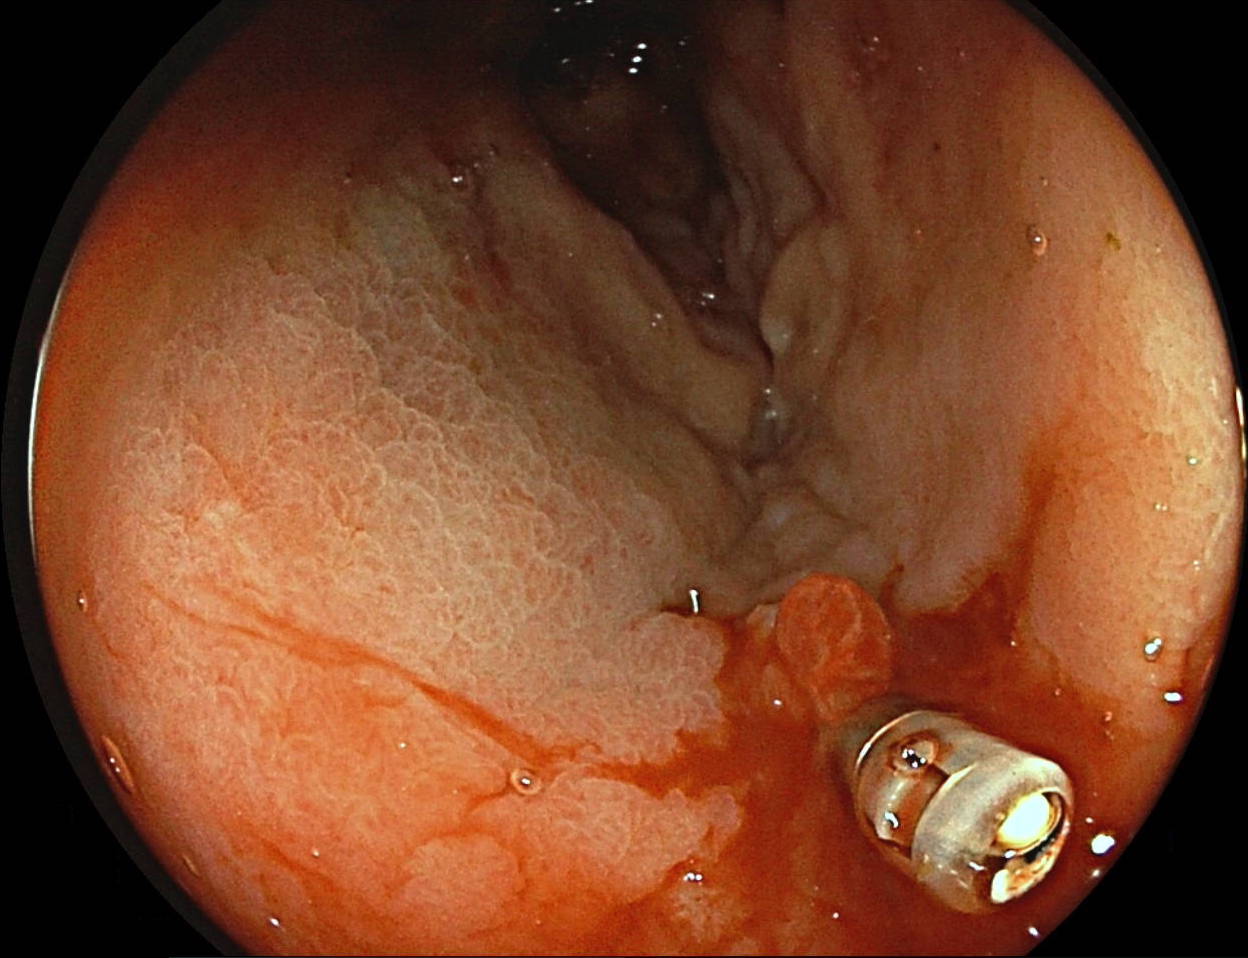

An unexpected (un)friend? Colonoscopy may still be the answer João Estorninho, Francisco Portela, Pedro Figueiredo Centro Hospitalar e Universitário de Coimbra A 64-year-old woman with an extranodal large B-cell lymphoma presented with massive pulsatile hematochezia. Despite resuscitation efforts, she maintained hemodynamic instability and performed two consecutive angiographies showing bleeding from rectal arteries which were superselective embolized with apparent success.Two days later, pulsatile hematochezia recurrence arose. A rectosigmoidoscopy showed a small ulcer in the rectum where we found a metallic pointed object crossing the rectal mucosa and on the opposite site an actively bleeding vessel (figure 1). An endoclip was applied with success (figures 2-3). This was the first report of a microcoil being identified during colonoscopy. Outras fotos: Fotografia Fotografia Fotografia Fotografia Fotografia Fotografia Fotografia Fotografia Fotografia Fotografia Fotografia Fotografia Fotografia Fotografia Fotografia Vídeo Vídeo Vídeo Vídeo VídeoError

An unexpected (un)friend? Colonoscopy may still be the answer